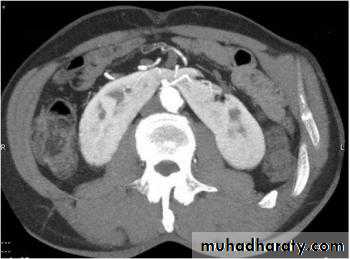

Pelvic kidney

This represents a form of renal ectopia. Prevalence is 1 in 2000–3000, withboth sexes affected equally.

The left kidney is affected more often than the right, and bilateral cases

are seen in <10%. The affected kidney is smaller, with the renal pelvis

positioned anteriorly (instead of medially), and the ureter is short but

enters the bladder normally.

Pelvic kidneys lie opposite the sacrum and below the aortic bifurcation

and are supplied by adjacent (aberrant) vessels (see Fig. 7.3). There is an

increased risk of congenital anomalies, including contralateral renal agenesis

and genital malformations.

Most cases are asymptomatic. Diagnosis is made on renal ultrasound

scan, IVP, or renography. Complications include obstruction, hydronephrosis,

and infection.